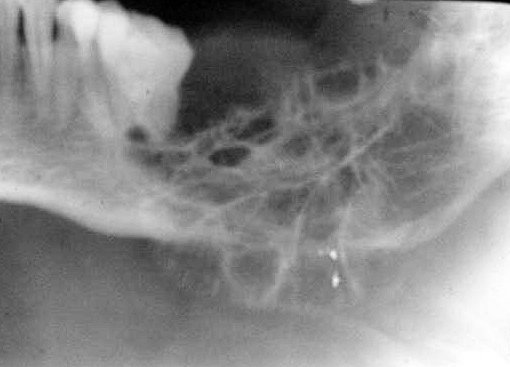

- Small lesions are usually unilocular, and larger lesions are multilocular.

- Well-defined margins.

- Adjacent teeth: often displaced or impacted. Root resorption is a common finding.